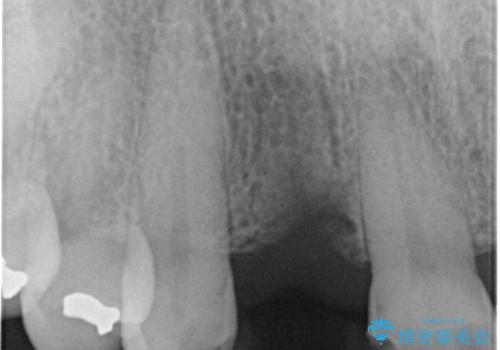

- 前歯のインプラント治療を検討して様々医院を探していたところ、1回の手術で治療ができるとのことで来院された患者様です。

長期間の治療と外科処置の回数が多くなることを懸念して、なかなかインプラント治療に乗り出せなかったそうですが、1DAYインプラントというものがあることを知り、当院にいらっしゃいました。

仮歯を事前に用意し、インプラント埋入時に即日で仮歯を装着する、即時荷重インプラントの計画で治療を進めて行くこととしました。